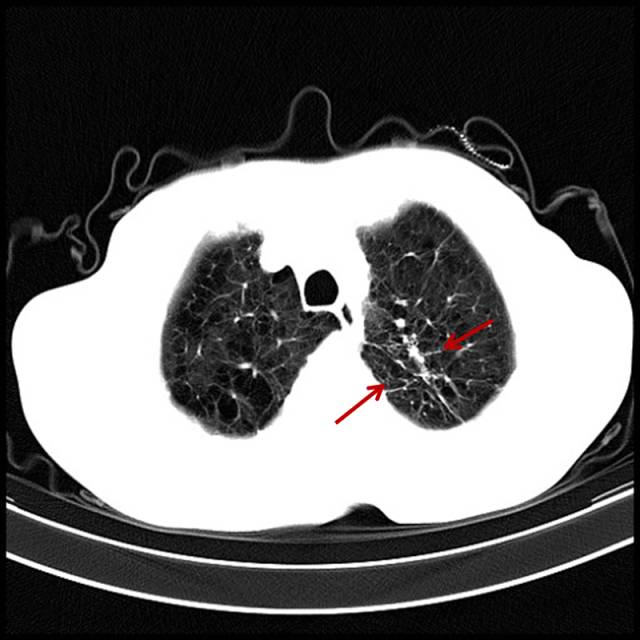

吸烟导致的轻度肺气肿

男,32岁,16岁开始吸烟。

图片

图5

肺的周边密度已经变低,周边纹理变细、消失,这时肺功能受到影响,详细询问病史,有气短症状。比如原来上五层楼气喘吁吁,现在上三层楼既能感到上气不接下气,症状往往被忽略,尤其是年轻人,不会以为自己吸烟会得肺气肿,这部分人也是最难戒掉烟的。与这类患者交谈时,也知道吸烟不好,但往往不以为然。此类患者多见于年轻人,属于亚临床患者。